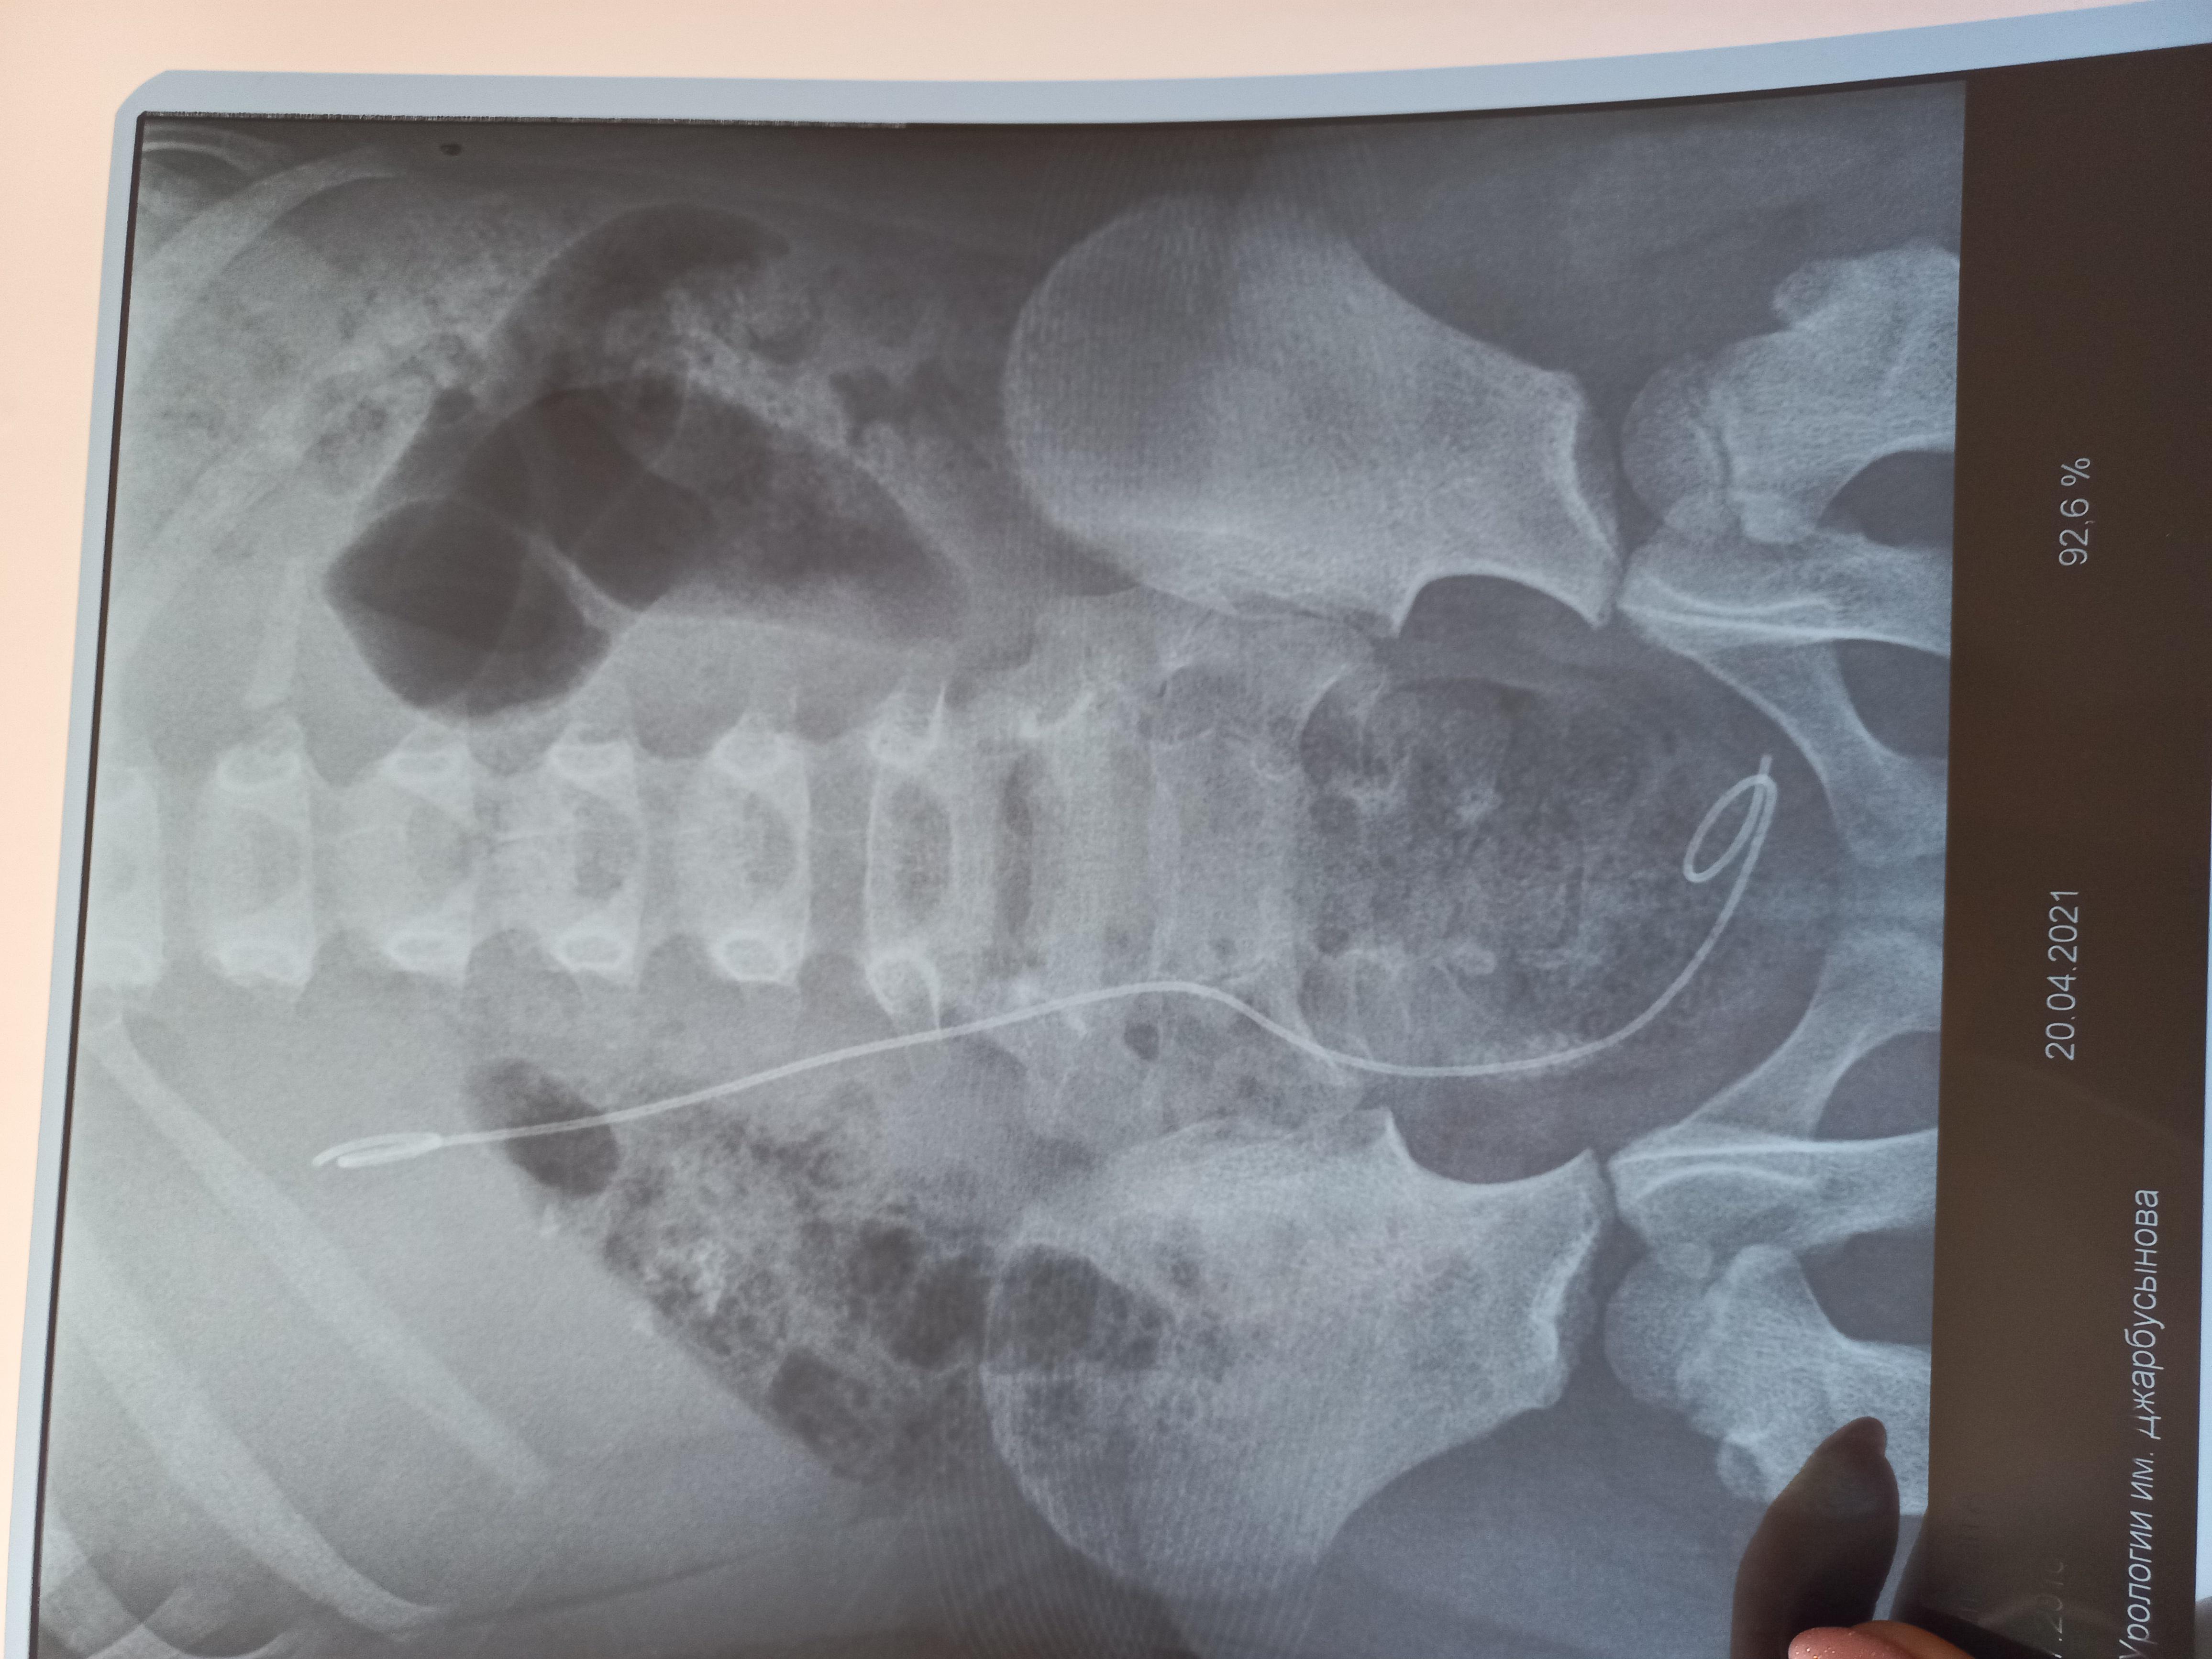

Здравствуйте! У моей дочери(5 лет)в феврале этого года обнаружили камни в почках фосфаты и оксалаты размером 1.6 мм и 0.6 мм, плотностью 1300 и 600 едХ. В марте была произведена операция по дробилению камня-ретроградная литотрепсия с установкой стент-катетора, в апреле трансуретральное устранение обструкции из мочеточника и почечной лоханки с заменой стент-катетора. Через неделю после выписки с больницы выпадает стент-катетор и в результате развивается гидронефроз. В начале мая опять же ставят стент-катетор и опять же он выпадает. В конце мая опять же производят операцию ЭУВЛ без установки стент-катетора. Последние снимки УЗИ показали, что камни ещё присутствуют в лоханке и в нижней чашки 7.6, 5.9, 5.8, 5 2,3.7, 4.9. Как вывести эти камни из почки и как можно выявить причину образований этих камней? Какие лекарства необходимо принимать, чтоб растворить камни?

Здравствуйте! Судя по представленным документам, Вашу дочь лечат высокопрофессиональные доктора и хирурги. При имеющейся ситуации вопрос о "растворении" конкрементов не идёт. Действительно, одномоментно вывести все фрагменты при естественных малых размерах мочевыводящих путей у ребёнка затруднительно. Поэтому приходится прибегать к неоднократным эндоскопическим процедурам, что, однако позволяет избежать более травматичного открытого хирургического вмешательства. Не исключено, что будет предложено очередное эндоскопическое вмешательство. К сожалению, вряд ли возможен вообще неинвазивный метод лечения в данном случае.